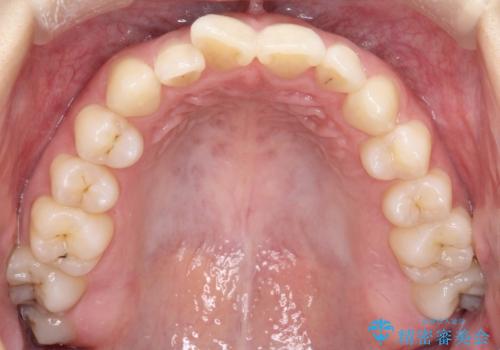

右下第二小臼歯の舌側転移の改善

- 患者様は、右下第二小臼歯が舌側に転移していることが主訴でした。診断の結果、抜歯を伴う矯正治療も検討しましたが、奥歯の遠心移動とIPR(インタープロキシマルリダクション)を行うことで、非抜歯で矯正を進めることが可能であると判断しました。治療計画では、審美ワイヤーを用いた2年間の治療で、歯列を整えつつ、臼歯関係や正中のバランスを維持しながら進めました。

非抜歯矯正では、歯の動きを慎重に調整することが求められます。本症例では、奥歯を遠心に移動させることで、舌側に転移した右下第二小臼歯の位置を改善しました。また、IPRを行うことで歯間スペースを確保し、無理なく歯列の調整を行いました。非抜歯での治療は、特に臼歯関係や正中を保ちながら治療できるというメリットがあり、最終的にはバランスの取れた歯並びを実現できました。審美ワイヤーを使用したことで、治療中も目立ちにくく、患者様の見た目にも配慮した治療を行いました。